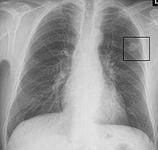

老年人肺癌癥狀

• 老年人肺癌

628健康網為您分享有關老年人肺癌的癥狀,老年人肺癌的治療方法,老年人肺癌的預防知識,老年人肺癌的癥狀圖片,老年人肺癌...